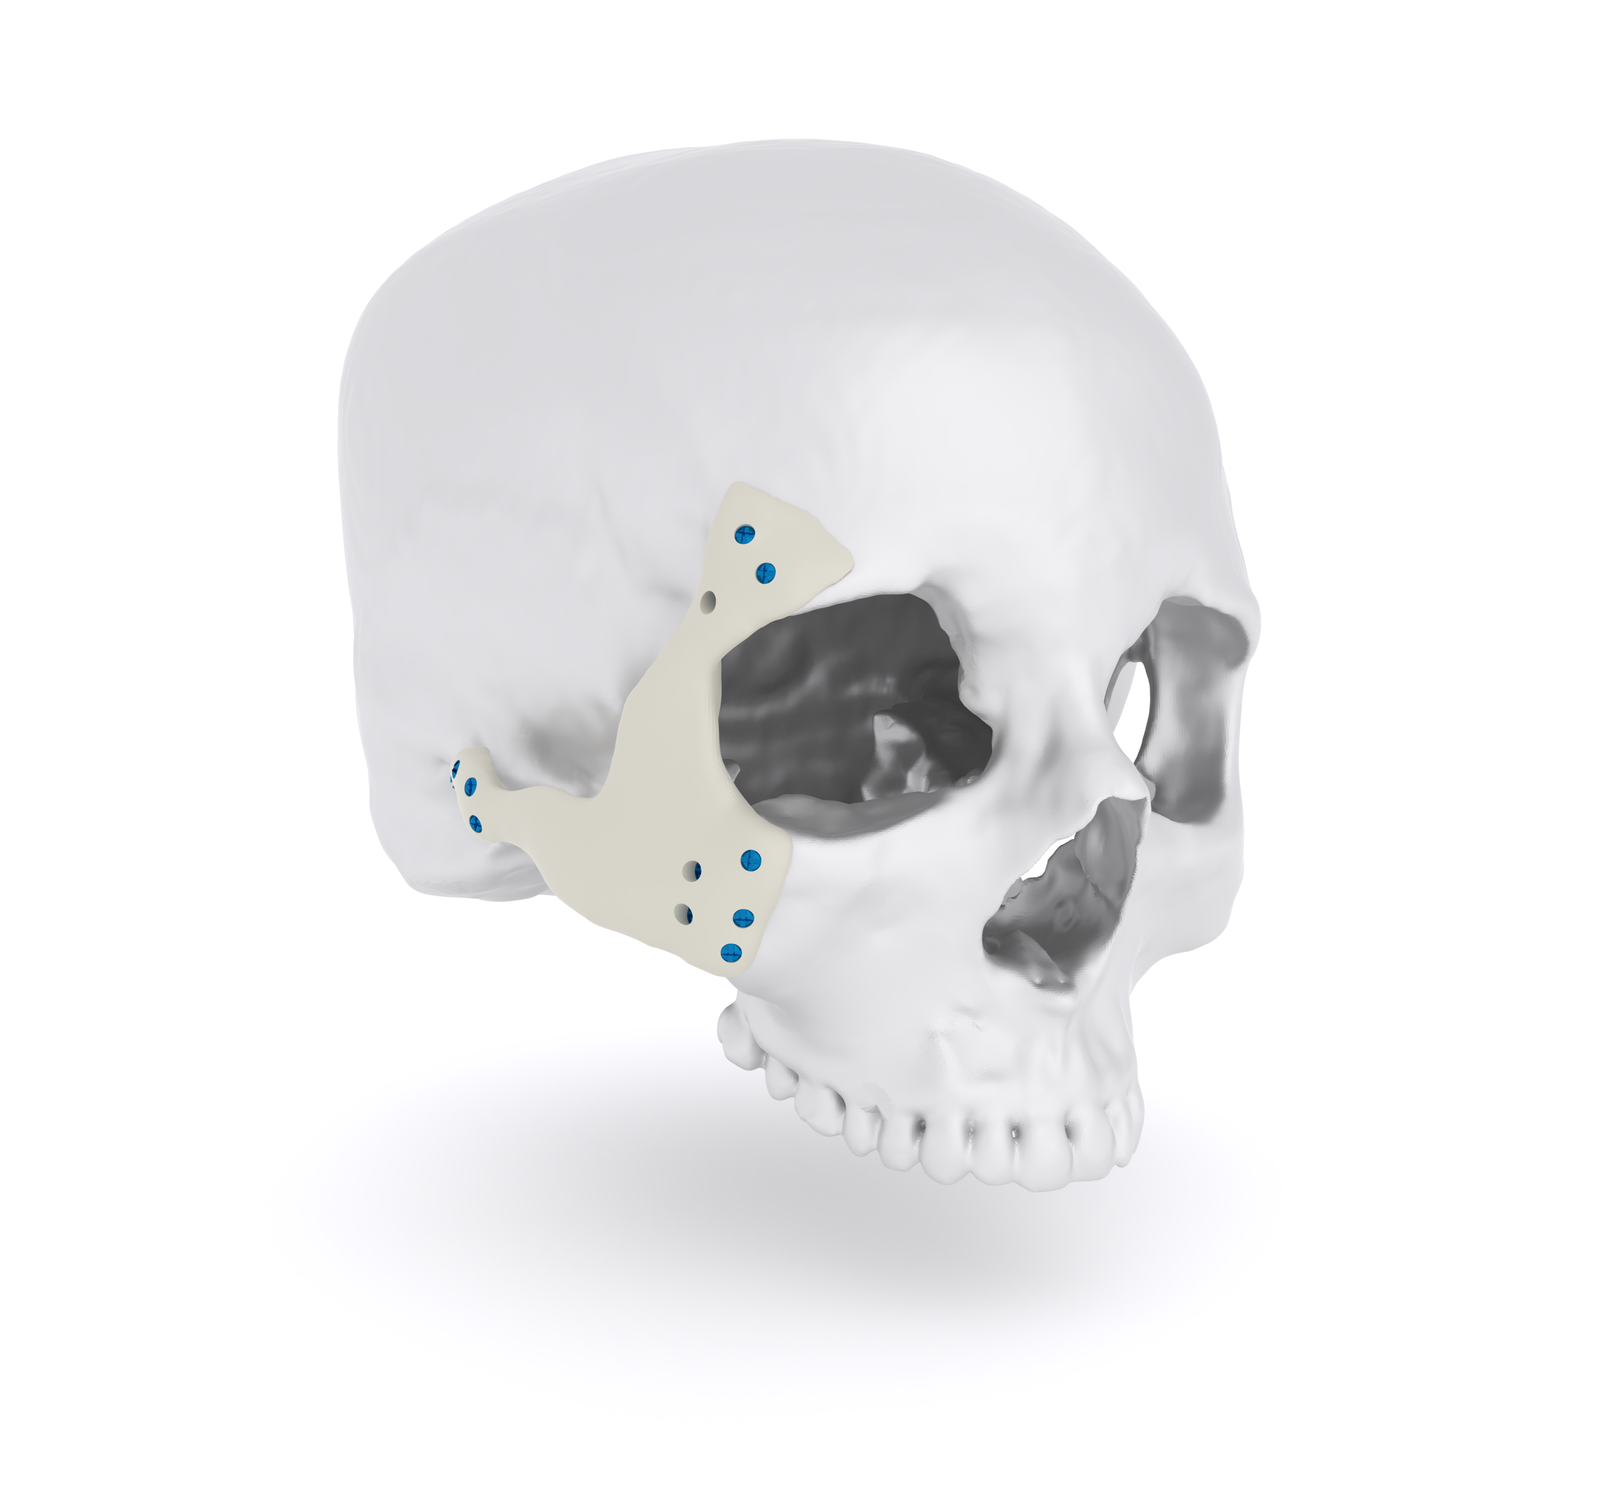

Product Overview

Overlay Titanium Implants offer a lightweight, durable solution designed to precisely cover moderate cranial bone defects. These implants are contoured to overlap the defect margins, providing stable fixation and restoring the natural shape of the skull.

This implant is ideal for stabilizing complex fractures, correcting enophthalmos, and restoring orbital volume. Multiple fixation points allow for secure placement, while the biocompatible titanium ensures long-term safety and stability. Available in standard configurations with options for patient-specific customization.

Benifits:

- Reconstructs the cheekbone zygoma and orbital floor after trauma, tumor removal, or congenital deformities.

- Maintains proper eye alignment and prevents exophthalmos (sunken eye appearance).

- Restores natural facial contour and symmetry, improving appearance and self-confidence.

- Minimizes facial flattening or deformity after injury or surgery.